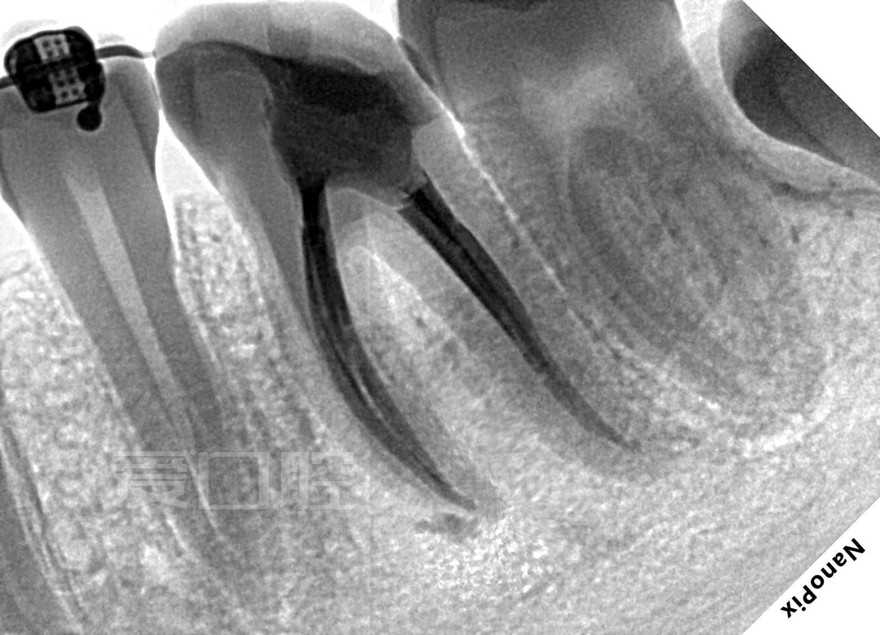

看个根充 —— 下6

by Paco CG